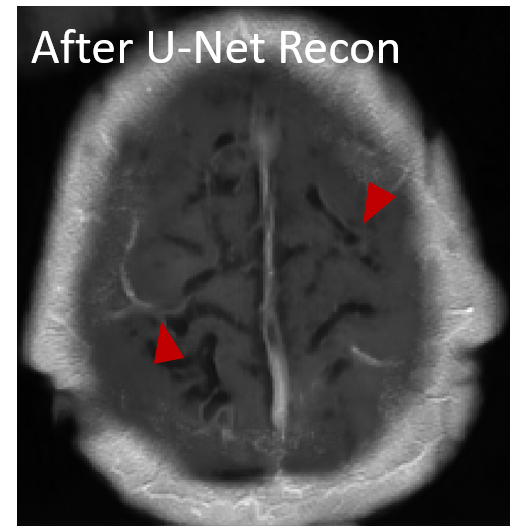

The reconstructed images from the learned trajectories using radial trajectory were demonstrated in Figure 4. These images were compared with the images directly reconstructed using fixed trajectory. The framework was slightly modified by removing the trajectory optimization network and only training the end-to-end reconstruction U-Net using the standard supervised learning approach. The qualitative evaluation of brain images proves the improved image reconstruction using our proposed method. As illustrated in Figure 4, the reconstructed images from learned trajectories are consistently better than those from the fixed trajectories for each type. More specifically, the learned radial trajectories provided improved reconstruction performance compared to their fixed counterparts in Figure 4 for the brain images at the AXT1POST sequence (More results in Appendix). Notably, the intermediate images directly obtained from the RSS reconstruction were shown at the top row of Figure 4 for the learned and fixed trajectories. It is evident that the learned trajectory can better remove structural and aliasing artifacts and provided more realistic image features and accurate image contrast than that of the fixed trajectory at the same level of acceleration, indicating the efficacy of the learning-based trajectory optimization.